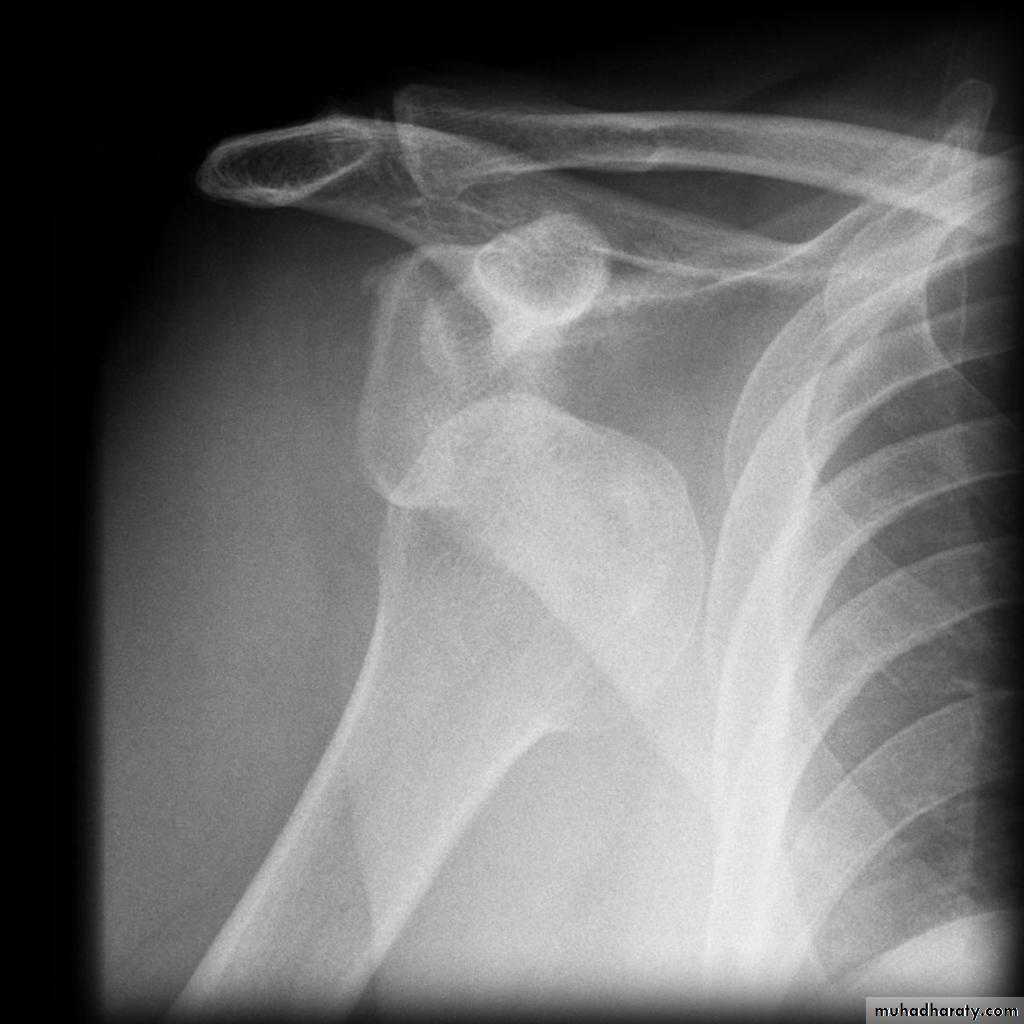

40 years male fall on out streched hand

Radial nerve palsy after reduction